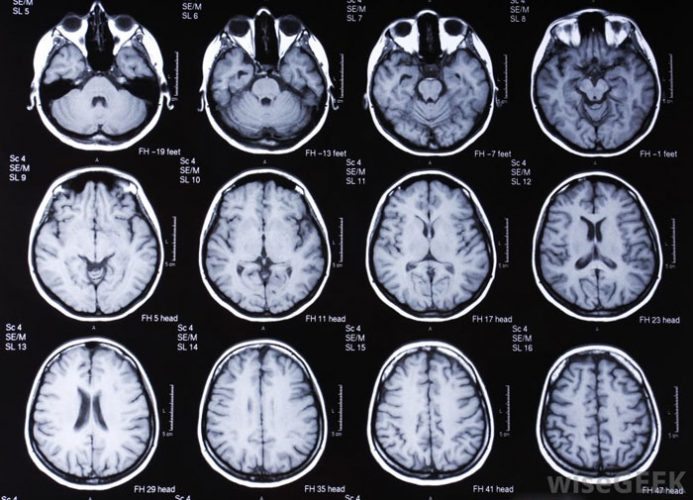

- МРТ головного мозга;

- Рентгеновское исследование. Для исключения органических поражений головного мозга, которые могли вызвать усиление ощущений при восприятии ароматов, назначается компьютерная томография. При недостаточной информативности метод дополняют проведением МРТ для точной визуализации мозговых структур.